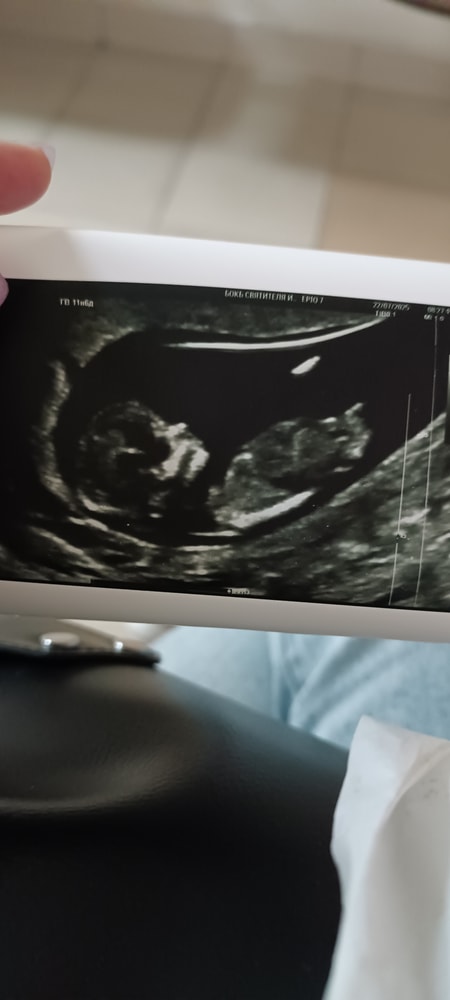

Анализы, скринингиПросто делюсь здесь, что прошла первый скрининг, сказали, что по УЗИ всё хорошо, осталось подождать результаты крови. Врач сказала, что всё хорошо , зато медсестра сказала, что у нашей печенюхи не нос, а шнобель. 😡 У самой у нее шнобель, а я как будущая мать вижу прекрасный носик 😀 фотки в комментариях